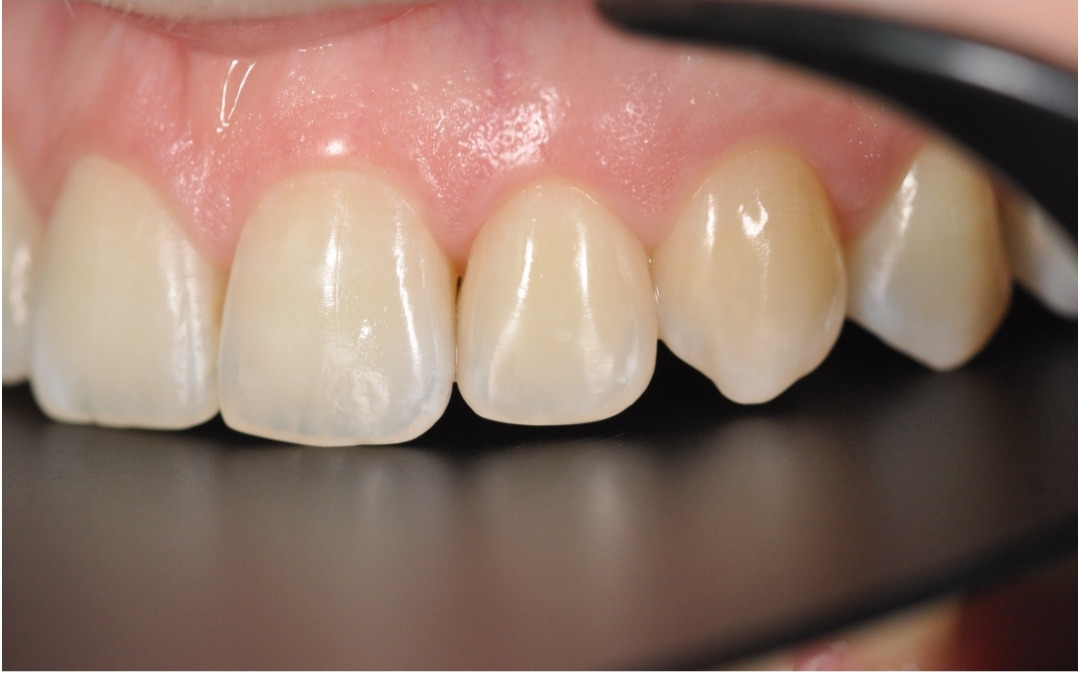

Этап №4

Финишная реставрация.

После снятия брекет-системы стоматолог-терапевт провела художественную реставрацию формы боковых резцов, добившись идеальной гармонии и естественности улыбки.

Эстетика

Исправлен прямой прикус, восстановлена форма резцов, а улыбка стала не только красивой, но и здоровой с точки зрения биомеханики.